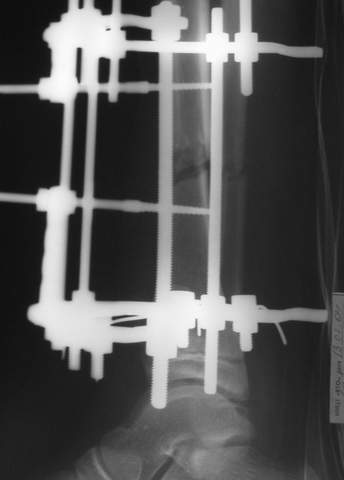

Под рукой прилагаемый пример. Как видите, "стриптиз-аппарат" (шутка проф. З.К.Башурова): 3 кольца-2 кольца-2 полукольца. В случае, который представил Евгений, характер повреждения позволил бы сразу использовать аппарат на основе 2 колец; в крайнем случае прокс. опора м.б. демонтирована сразу после репозиции.

МТ мы используем, конечно, не только на голени. В прилагаемом примере у парня при поступлении была наружная ротация 40 гр. и "полумертвый" коленный сустав. Можно был бы, конечно, до конца использовать полную компоновку. Но для того он и есть метод выбора.